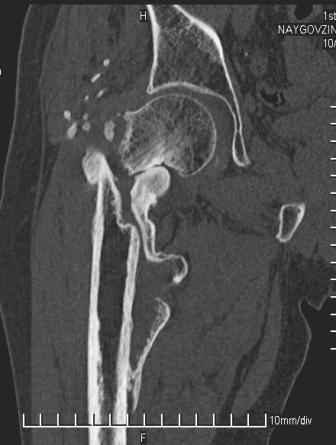

Больной Н. 44 года травма 1,5 года назад июнь 2008 года чрез-под вертельный перелом правого бедра. Во время лечения у больного развился алк. делирий, проводилось консервативное лечение перелома.

Беспокоят боли, укорочение конечности.Укорочение 3 см. Ногу поднимает, сгибание ограничено, ротационные движения в полном объеме.На КТ перелом сросся за счет костной мозоли.Что делать?

Протез? Если «да» Можно ли обойтись стандартной ножкой Corail?

Или межвертельная остеотомия?

Уважаемый Глеб! Укорочение наверное побольше, да и наружно-ротационная установка скорее всего присутствует. Суставная щель прекрасная, головка живее всех живых. Ратую за подвертельную с латерализацией: исключает нарушение механической оси («исключает вальгус в коленe»), максимально удлиняет без натяжения m.iliacus. Для иллюстрации остеотомия-переделка (слава богу не автопеределка) у мужчины 65 лет.